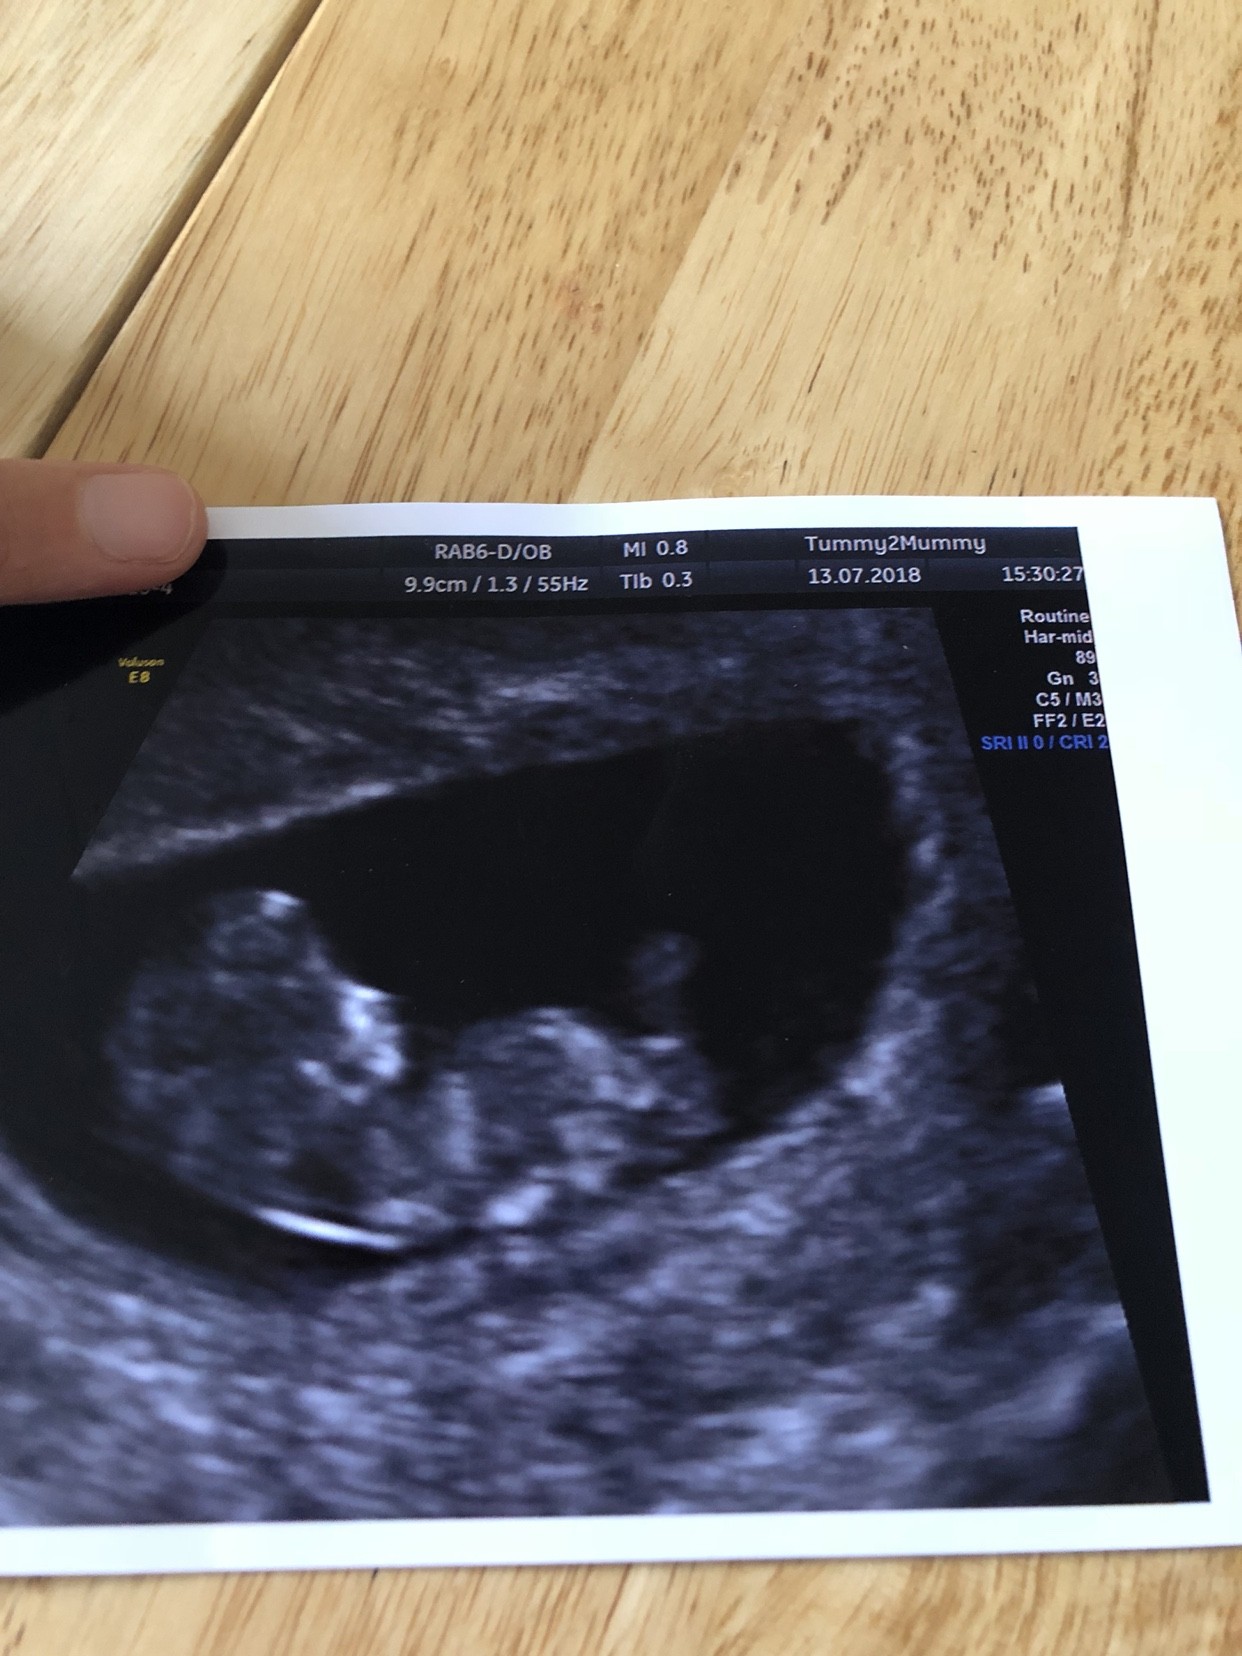

Dziewczyny ja tak na szybko, zdecydowałam sie na test NIPT, mam koszt w 80% refundowany przez ubezpieczenie w pracy wiec pomyślałam, czemu nie. Wyniki za 7 dni. Poszłam dzisiaj 10 +4, pobrali krew ale najpierw szybkie usg żeby potwierdzić tydzień ciąży. Wiec oto mój dzidziol Wiercił sie niemiłosiernie i cudnie było go zobaczyć [emoji4]

Dziewczyny ja tak na szybko, zdecydowałam sie na test NIPT, mam koszt w 80% refundowany przez ubezpieczenie w pracy wiec pomyślałam, czemu nie. Wyniki za 7 dni. Poszłam dzisiaj 10 +4, pobrali krew ale najpierw szybkie usg żeby potwierdzić tydzień ciąży. Wiec oto mój dzidziol 9.9 cm. Wiercił sie niemiłosiernie i cudnie było go zobaczyć [emoji4]